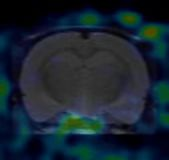

下(xià)圖為(wèi)30min顯像圖像